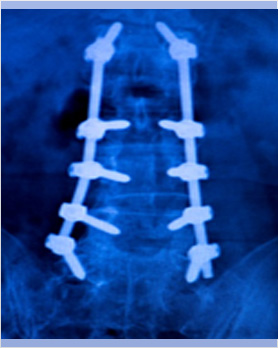

" 척추 수술 후 남은 통증, 통증추나로 해결하세요 "

- 척추 관련 수술 및 다양한 치료(약물치료, 물리치료 등)를 통해 1차적인 치료가 이루어졌음에도 불구하고 다시 목 통증, 허리 통증, 다리 저림 등이 나타나는 경우가 있습니다. 이 때 검사를 해보게 되면 실제 디스크 주변에 염증이 생기고 디스크가 튀어나와 재발한 경우(척추수술후유증 포함)부터 체형 및 근육 불균형에 이르기까지 다양한 형태로 통증 원인을 찾아볼 수 있습니다.

우리 몸은 레고 블록이 아니므로 문제 되는 디스크를 제거하거나 중간에 블록을 삽입한다고 해서 그 상태가 유지되는 것은 아닙니다. 특히 수술 이후 허리에 무리한 운동이나 작업 자세, 습관을 지속한다면 체형의 불균형이나 척추의 부정렬을 해소되지 않아 수술 후 후유증이 나타나는 경우가 많습니다. 척추 수술 후 통증추나는 수술 이후 재발 예방 및 관리를 위해 척추 관절 가운데 움직임이 제한된 관절이 다시 움직일 수 있도록 해주고, 근육의 균형을 잡아줌으로써 척추 스스로 정상적인 상태를 유지할 수 있도록 도와드립니다. 필요한 근육을 강화시킬 수 있는 운동 치료, 수술 후 발생한 어혈 제거와 약해진 뼈, 근육을 강화시켜주는 한약, 통증을 제어하는 침, 약침 치료 등 수술의 종류나 후유증에 따라 다양한 치료를 적용할 수 있습니다.